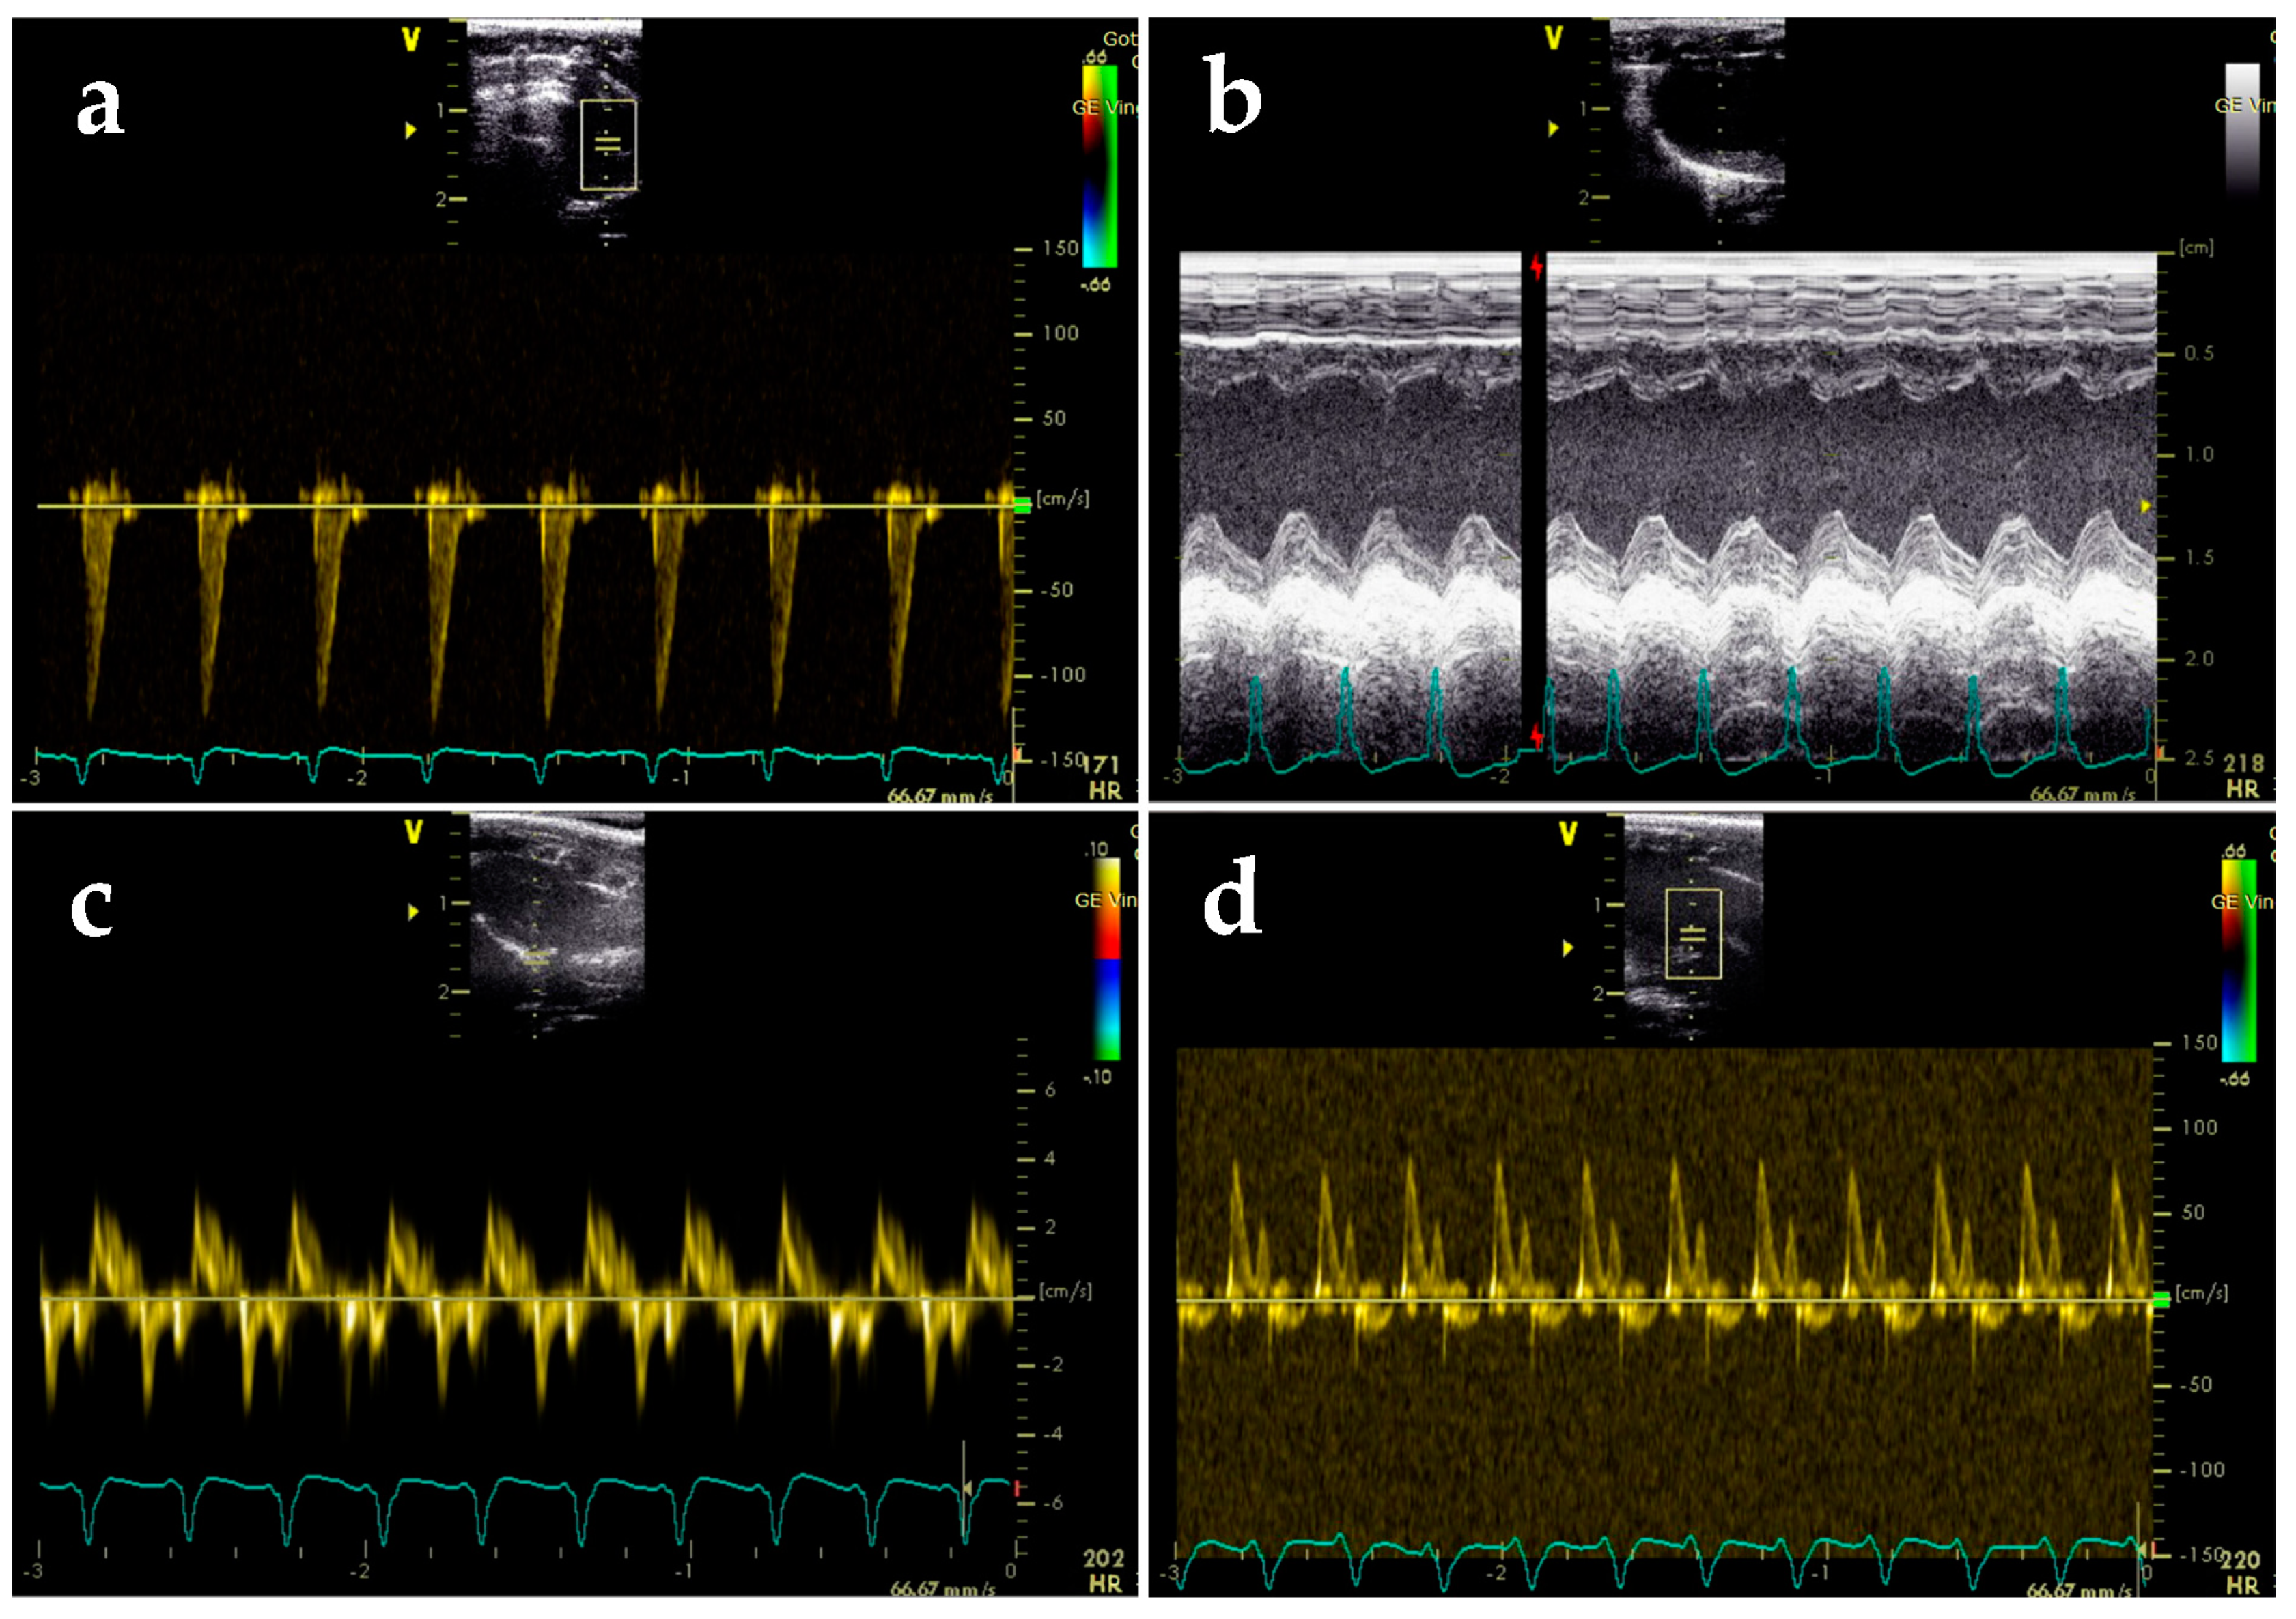

2.3. BGP-15 Enhances Diastolic Function Measured by Echocardiography

4.4. Echocardiography